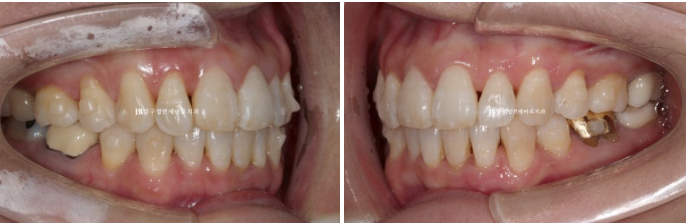

배열이 가지런해졌고 소량의 치간삭제를 통해 블랙트라이앵글도 줄었습니다.

단 위 앞니 높낮이 단차가 있어서 이 부분을 추가장치에서 해결하기로 했습니다.

뻗친 앞니 각도가 개선이 되고 나비치아 토끼이가 배열이 되었습니다.

24.01

이 정도도 충분히 좋지만 100점 목표를 위해 추가장치 제작을 합니다.